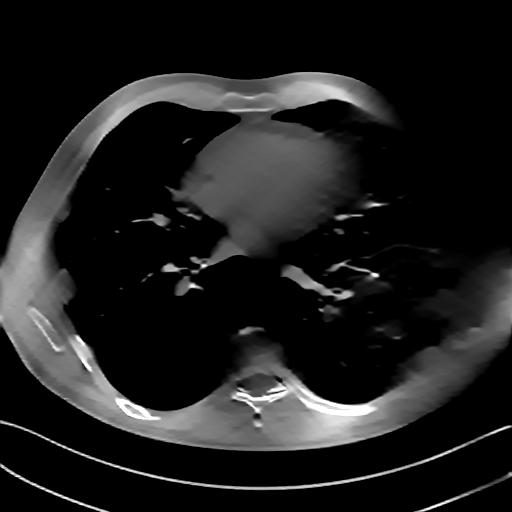

GT

FBP

HQS-CG

DuDoNet

Meta

Meta_re

EPNet

Qualitative Results Comparison. We also visualize the reconstruction results of these methods on AAPM-test and COVID-test datasets. As in the first three rows of Fig. 4, the reconstructed images from ours and retrained MetaInvNet show the best visualization quality on AAPM-test set across different angle numbers. Besides, our results show sharper details with the additional utilization of in the projection domain. When testing the reconstructed image on the COVID-test set, our result also gives sharper details but with more artifacts since the data distribution is very different. Although HQS-CG has achieved better quantitative results on the COVID-test dataset, the reconstructed image of their model in the fourth row is even smoother than FBP.